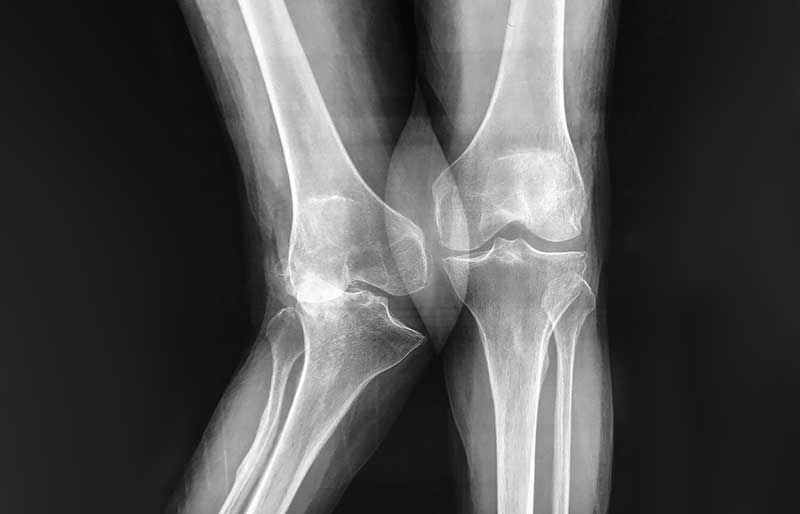

Operasi penggantian sendi lutut adalah suatu operasi untuk mengganti sendi lutut yang rusak akibat osteoartritis (penipisan tulang rawan) dengan sendi buatan yang disebut prosthesis. Penyebab utama kerusakan sendi lutut adalah osteoartritis (baca pen- jelasan tentang “Osteoartritis”) dan sendi yang paling sering terserang osteoartritis adalah lutut.

Operasi penggantian sendi lutut merupakan pengobatan terbaik untuk osteoartritis lutut stadium 3 dan 4. Ada empat tujuan operasi ini, yaitu menghilangkan rasa sakit sendi yang telah rusak, memperbaiki lingkup gerak sendi yang sebelumnya kaku dan terbatas, mengembalikan kemampuan penderita melakukan aktivitas harian tanpa rasa sakit, dan meningkatkan kualitas hidup sehingga penderita kerusakkan sendi dapat menjalani hidup secara aktif bebas dari nyeri sendi.